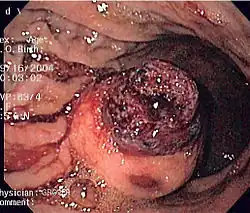

.jpg)

Small GISTs

Since GISTs arise from the bowel layer called muscularis propria (which is deeper to the mucosa and submucosa from a luminal perspective), small GIST imaging usually suggest a submucosal process or a mass within the bowel wall. In barium swallow studies, these GISTs most commonly present with smooth borders forming right or obtuse angles with the nearby bowel wall, as seen with any other intramural mass. The mucosal surface is usually intact except for areas of ulceration, which are generally present in 50% of GISTs. Ulcerations fill with barium causing a bull's eye or target lesion appearance. In contrast-enhanced CT, small GISTs are seen as smooth, sharply defined intramural masses with homogeneous attenuation.